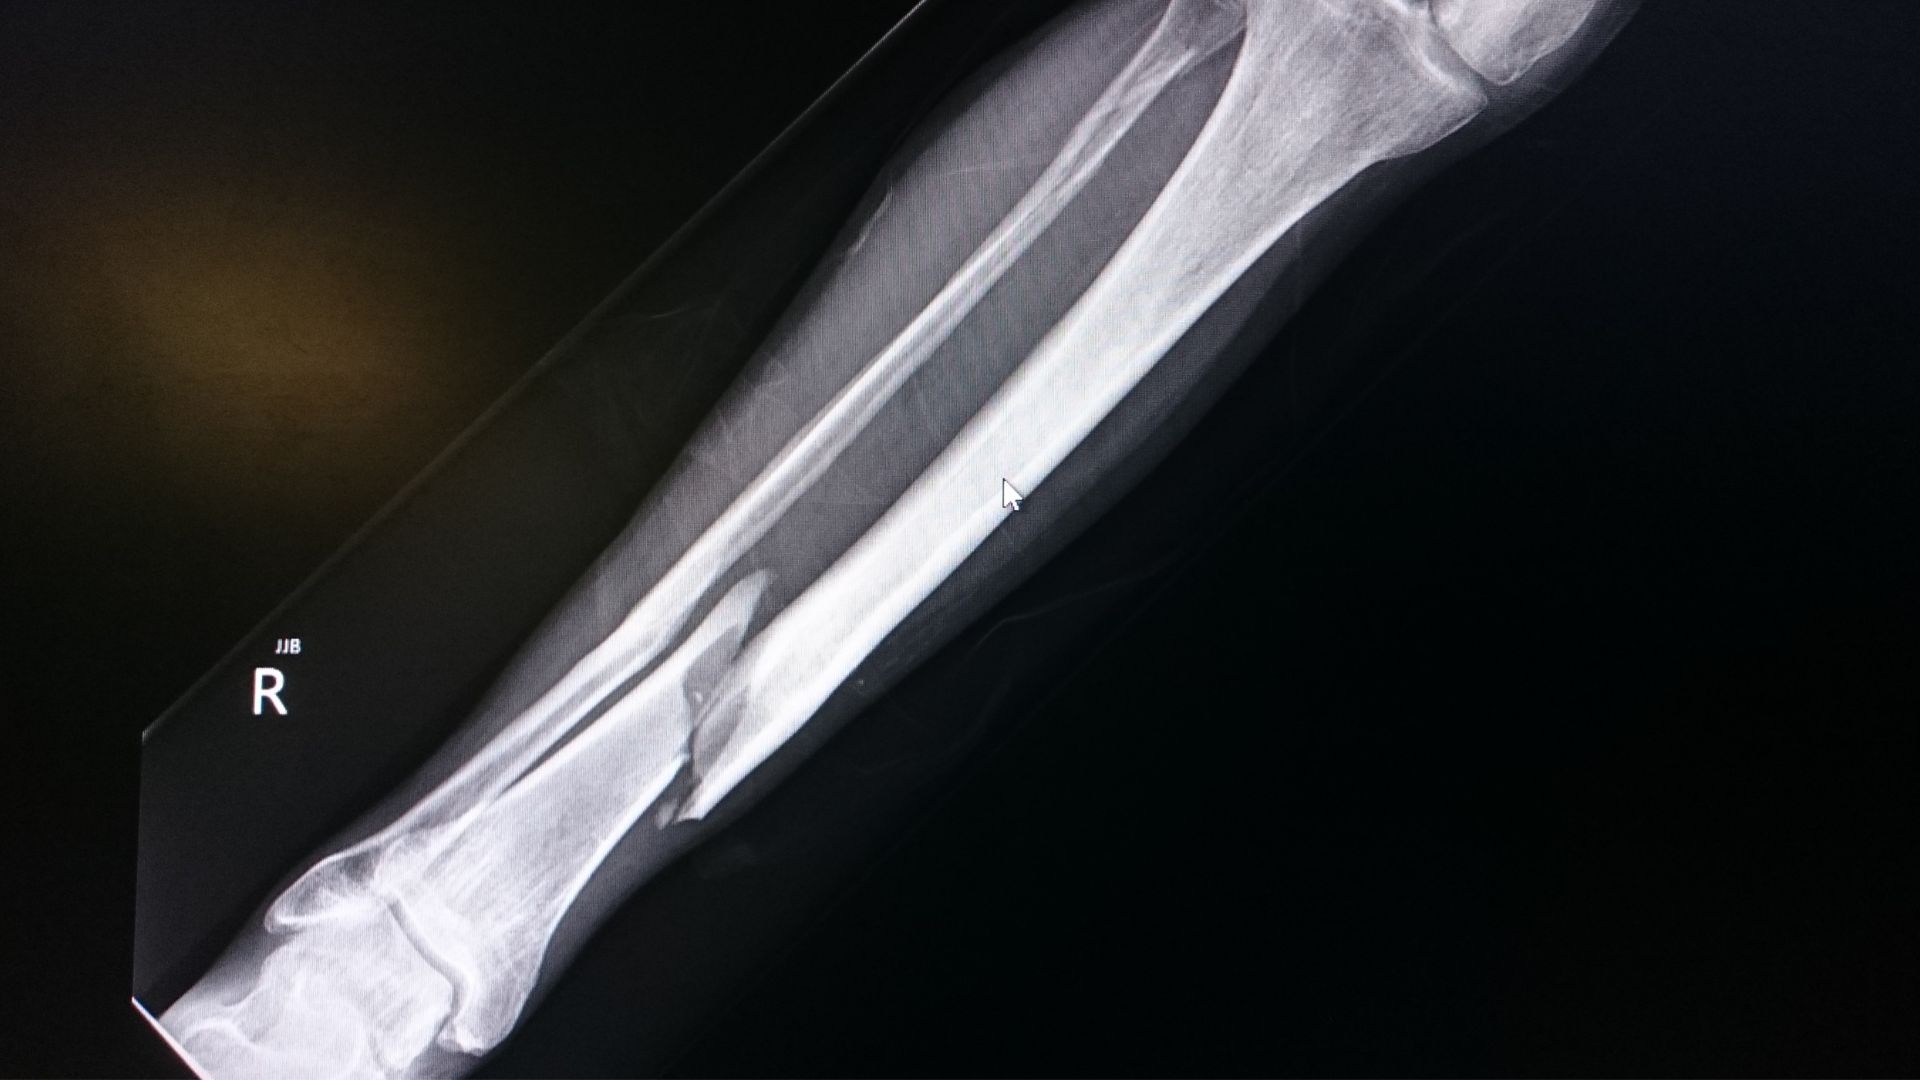

Blount’s disease

A growth disorder of the shinbone where bowing worsens over time. More commonly seen in:

Previous injury

A fracture affecting the leg’s growth plates can cause bowing in one leg.

- Blount’s disease

- Rickets

- Bone disorders

- Growth plate injuries